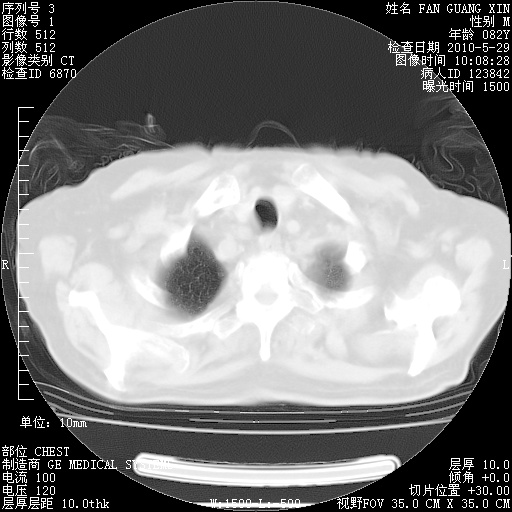

再治疗10天后的肺部CT

肺部体征:呼吸25次/分,心率100次/分,呼吸音增粗。无干湿罗音。

阅读此次胸部CT,肺间质渗出性改变较入院时有吸收。目前从体温、白细胞、中性分叶明显增高,肯定存在细菌感染(发生医院感染哦,若无消化道及泌尿系统等感染的依据,肺部感染可能大)。若你院头孢哌酮舒巴坦钠耐药率较高,同意你的方案,若48小时体温仍高,可考虑使用碳青霉稀类抗菌药物,同时可予超声雾化、注意滴数时加大液体量。白蛋白33.30g/L较低哦,需加强营养等支持治疗。